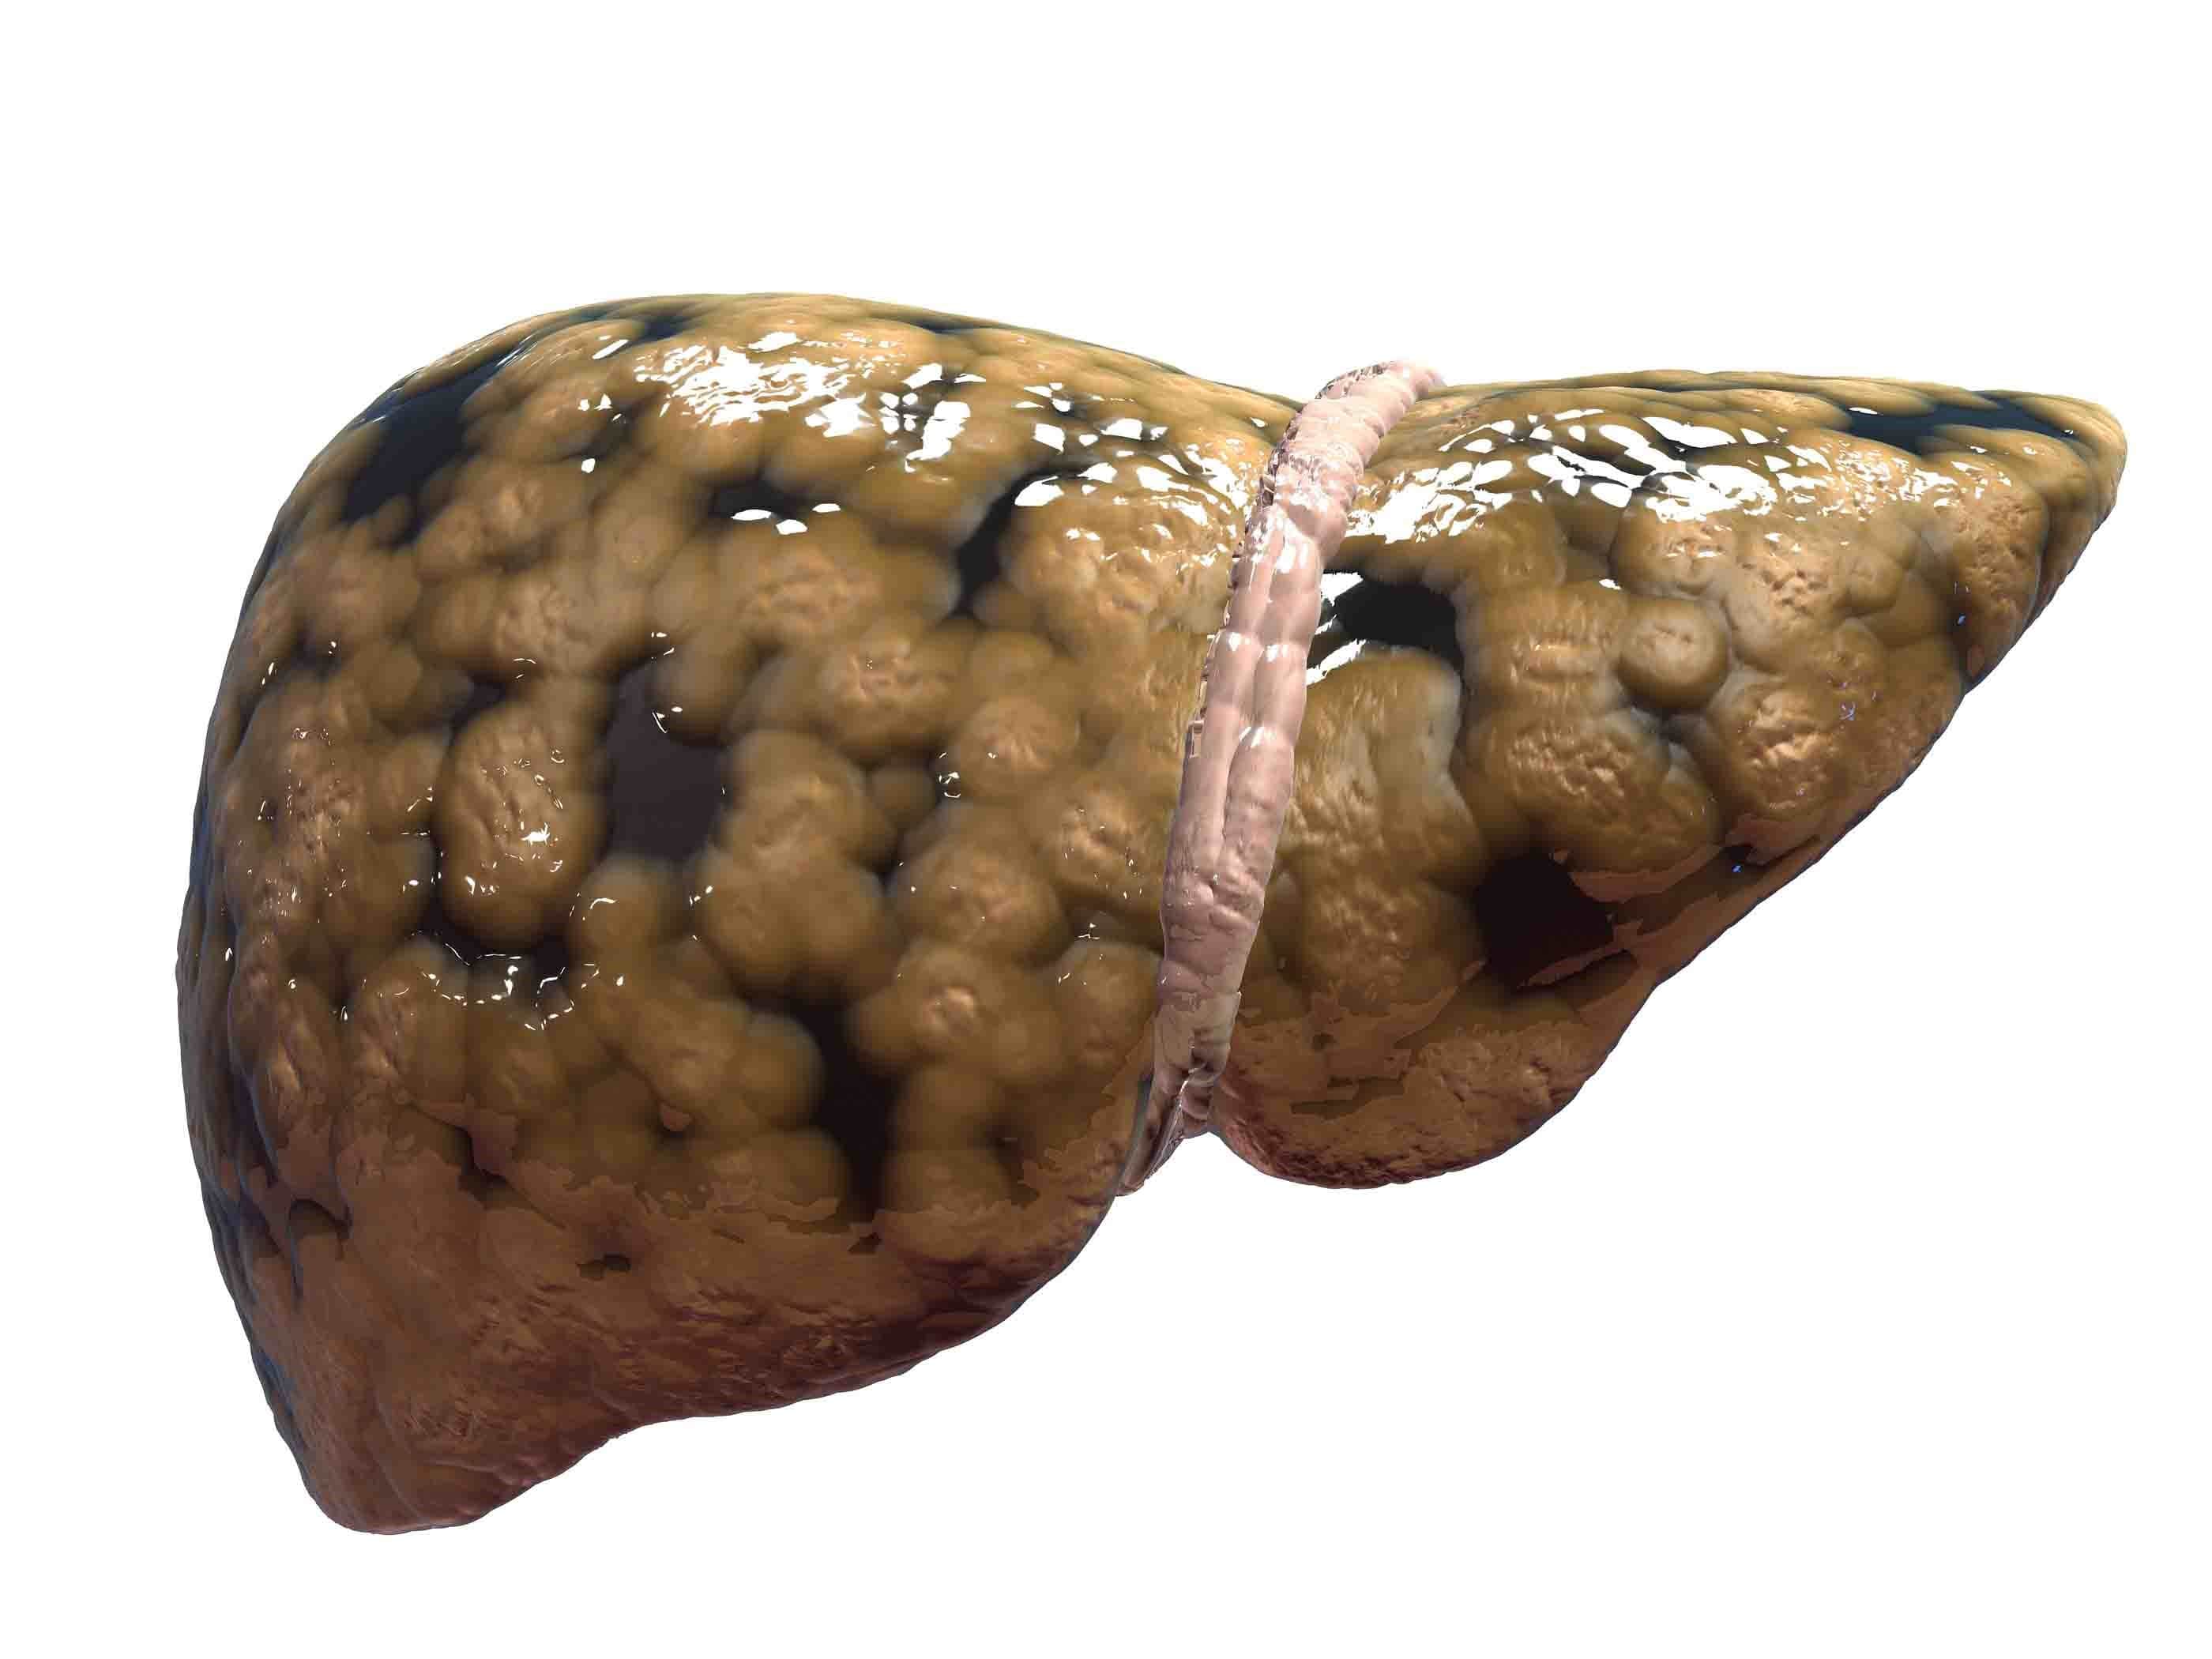

قیمت: 42٬000 تومان - دسته بندی فایل: پاورپوینتپاورپوینت بیماری های کبد

فروش ویژه پاورپوینت حرفه ای بیماری های کبد با تخفیف استثنایی فقط 48500 هزار تومان تعداد اسلاید : 20 اسلاید